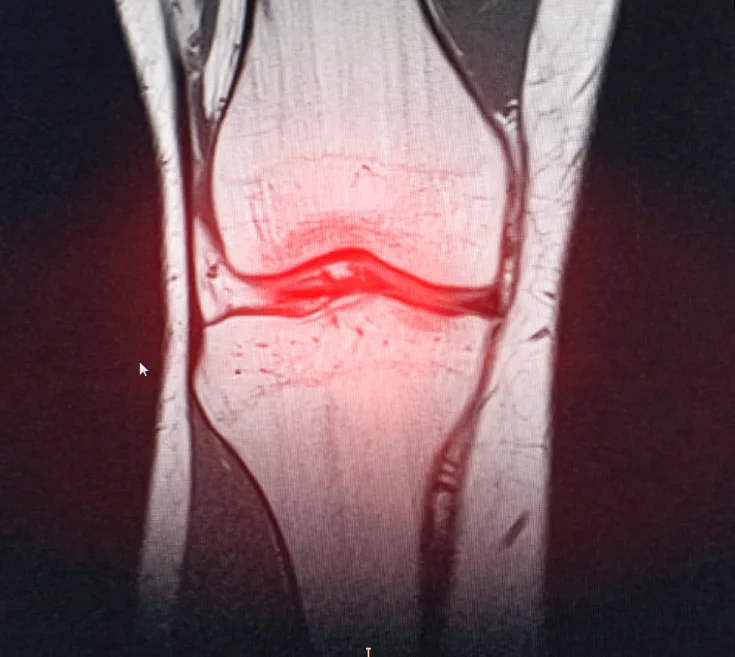

Le caratteristiche del liquido sinoviale che lubrifica le articolazioni, così come i suoi meccanismi d’azione, possono cambiare a seguito di un trauma articolare, con modificazioni che assumono un ruolo decisivo nella progressione dell’osteoporosi post-traumatica (PTOA).

Nell’esperimento in questione, le cavie animali (topi, in particolare) sono state sottoposte a una rottura non invasiva del legamento crociato anteriore, creando una situazione che potenzialmente si riproduce in maniera analoga negli esseri umani. Attraverso il sequenziamento a singola cellula dell’RNA, si è poi valutata la popolazione di cellule sinoviali e lo sviluppo di patologie indotte dalla PTOA.

Grazie alle indagini sono stati individuati 7 insiemi funzionali di fibroblasti, e anche la loro evoluzione nei casi di osteoporosi precoce e consolidata, evidenziando differenze significative tra persone sane, chi ha avuto un trauma articolare e chi soffre di artrosi. Altro elemento di grande importanza è la segnalazione sinoviale Wnt/β-catenina, che subisce un’alterazione a seguito dell’osteoporosi post-traumatica, favorendo di fatto l’insorgenza dell’artrite.